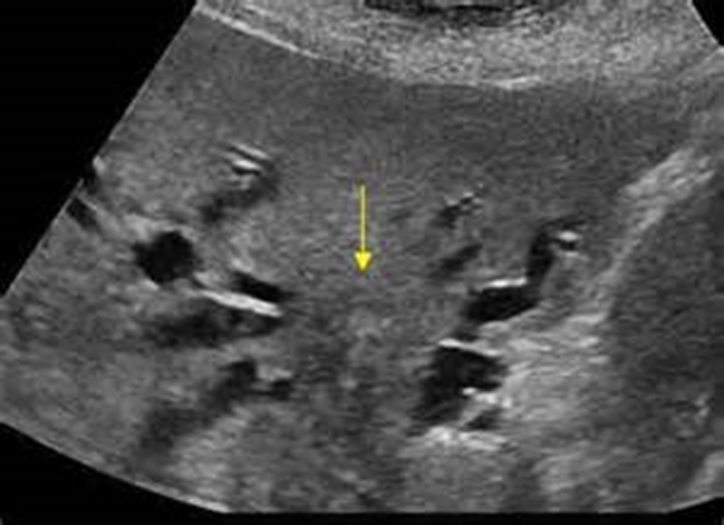

What is being shown in the image above?

Intrahepatic Cholangiocarcinoma